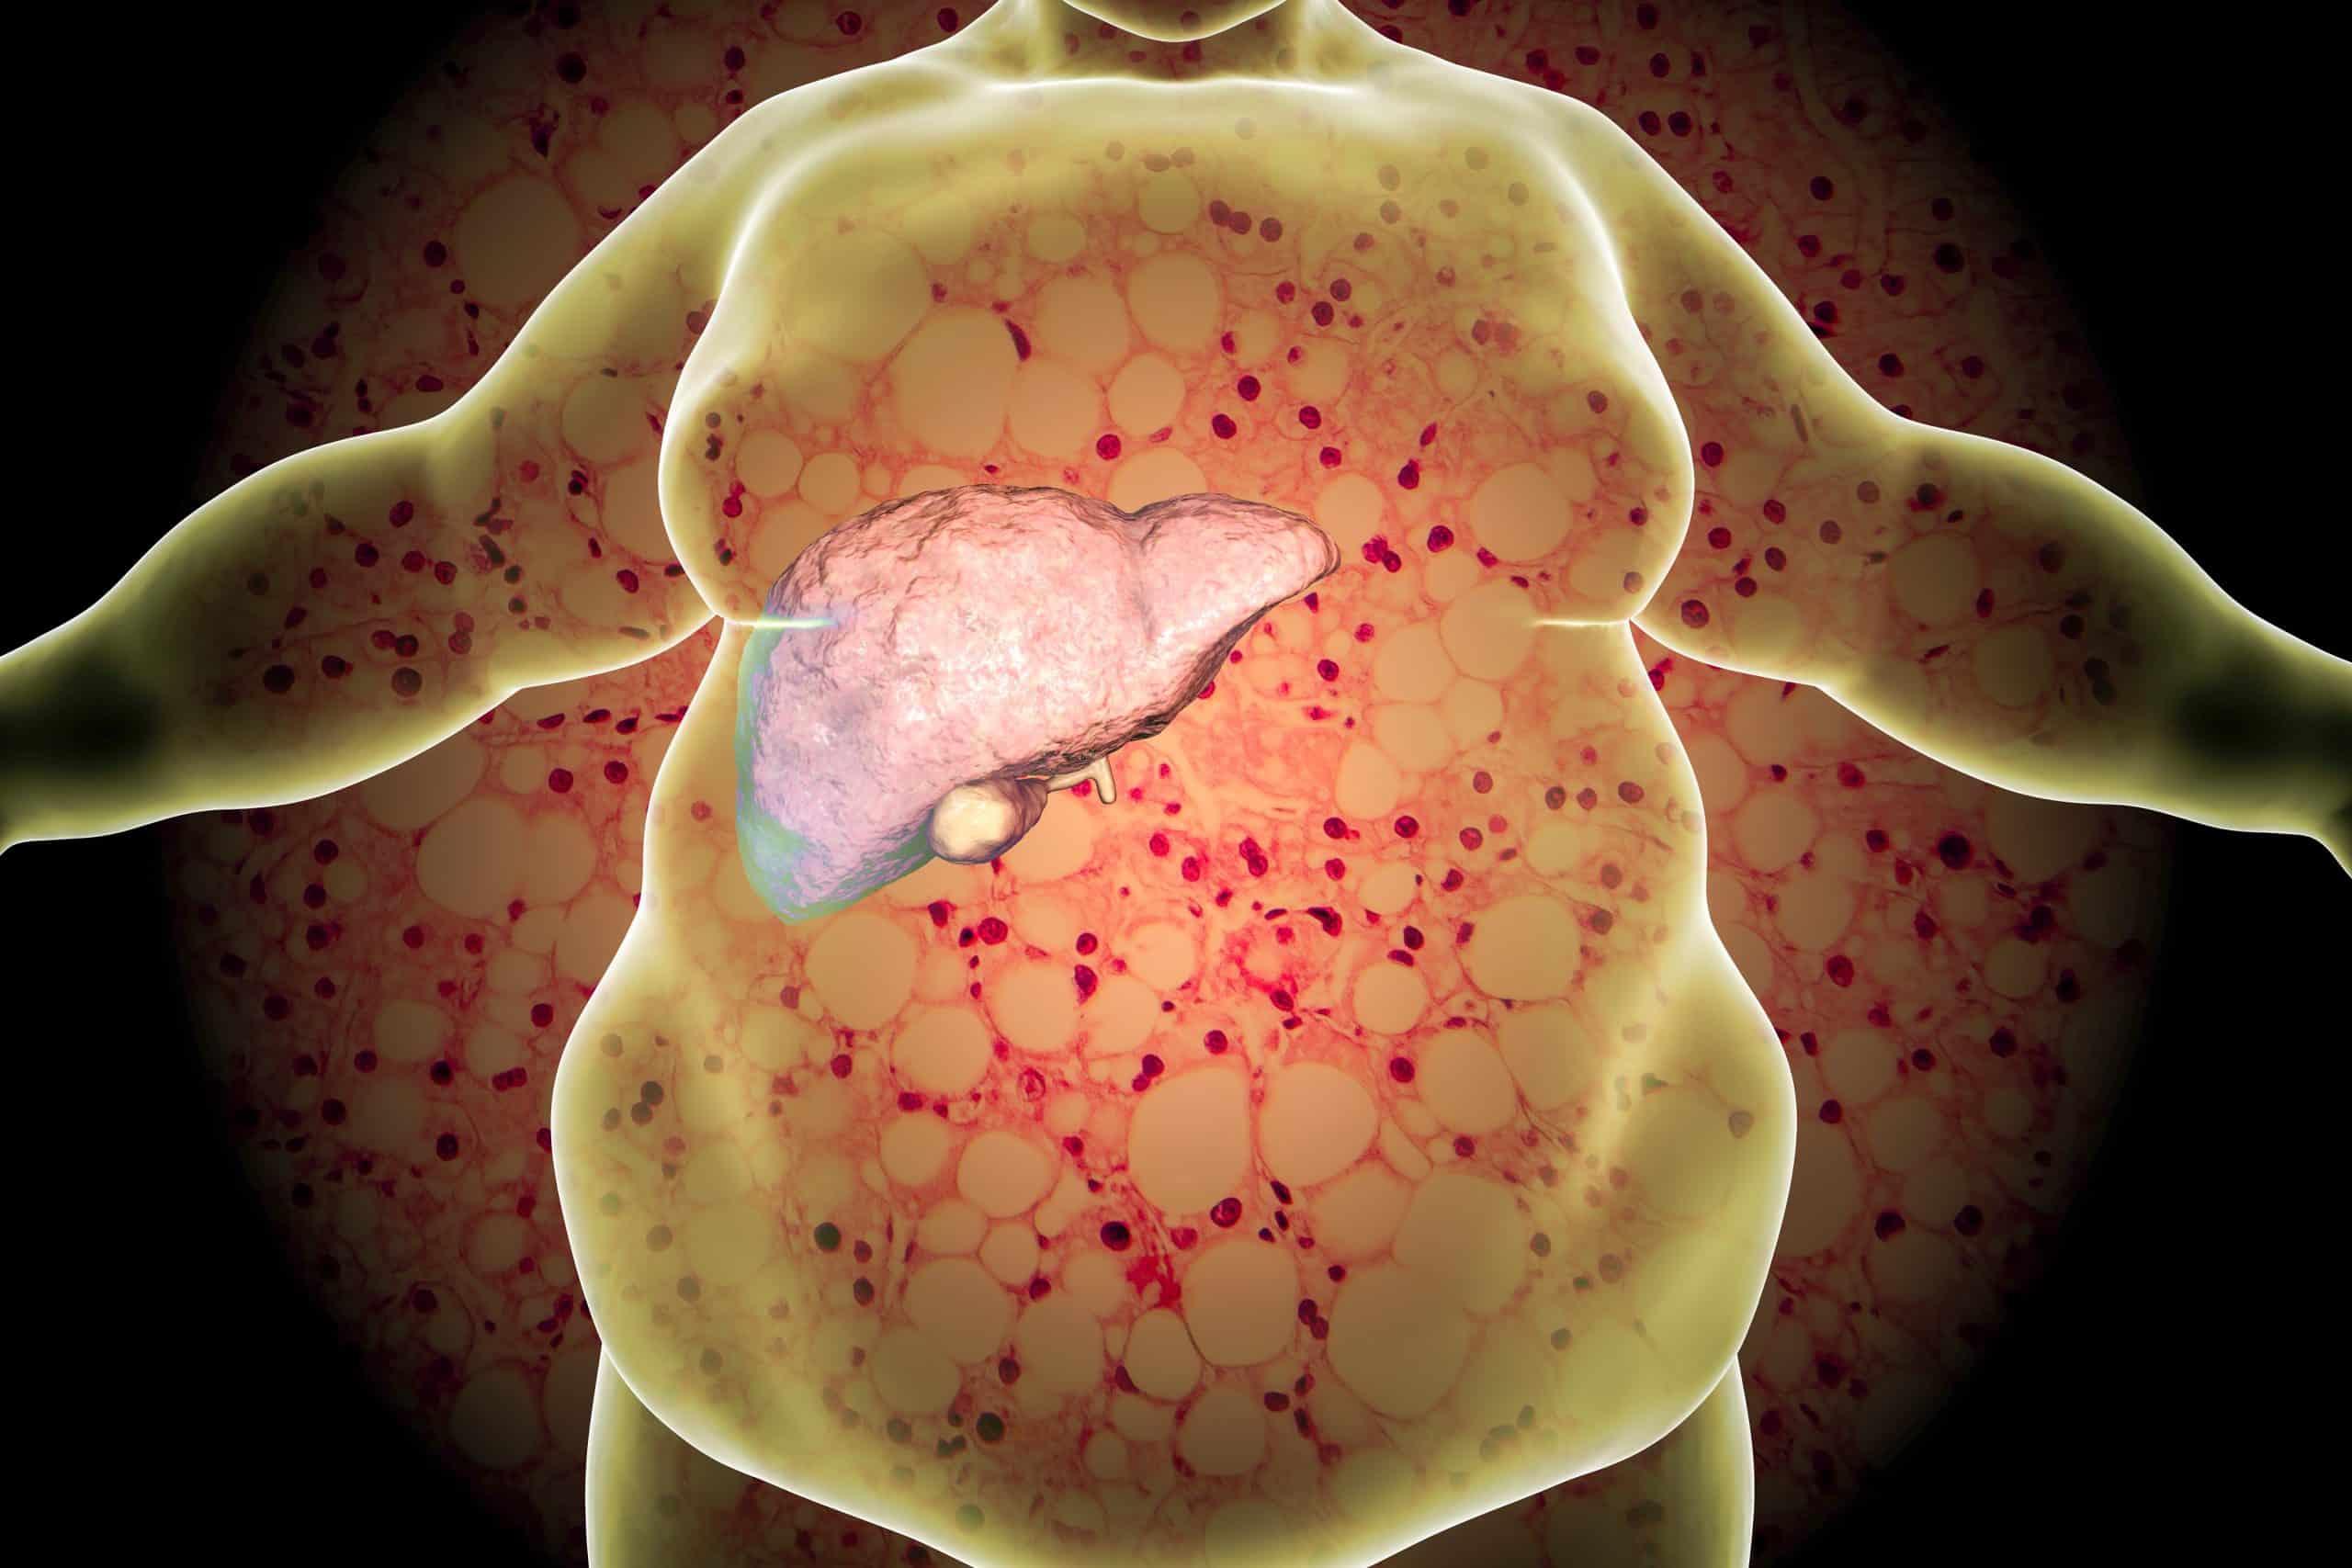

奇美醫院胃腸肝膽科主治醫生陳季杏說明,「非酒精性脂肪肝疾病(Nonalcoholic fatty liver disease, NAFLD)也就是俗稱的「脂肪肝」,脂肪肝的定義是指肝臟細胞內堆積了以脂肪為主的空泡(主要為三酸甘油脂),脂肪含量超過全肝臟重量的5%稱之。近年來,隨著飲食西化,脂肪肝和代謝症候群的病人比例也逐漸增加。

脂肪肝若未及時改善,時間一長,肝細胞可能會損傷,導致脂肪肝炎,甚至引發為肝硬化及肝癌等併發症,對肝臟造成嚴重傷害。有研究指出亞洲每1,000個脂肪肝當中,一年約有5.3人會死亡。

脂肪肝的定義是指肝臟細胞內堆積了以脂肪為主的空泡(主要為三酸甘油脂),脂肪含量超過全肝臟重量的5%稱之。